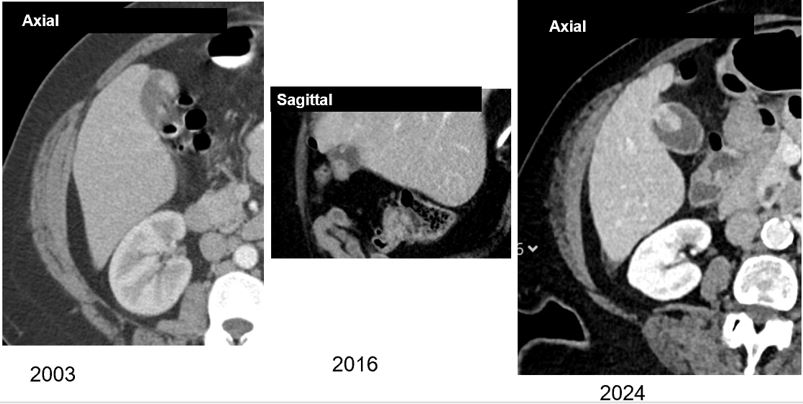

Challenge yourself with a biliary case: Adult woman with pancreatic adenocarcinoma undergoing restaging CT, reportedly asymptomatic